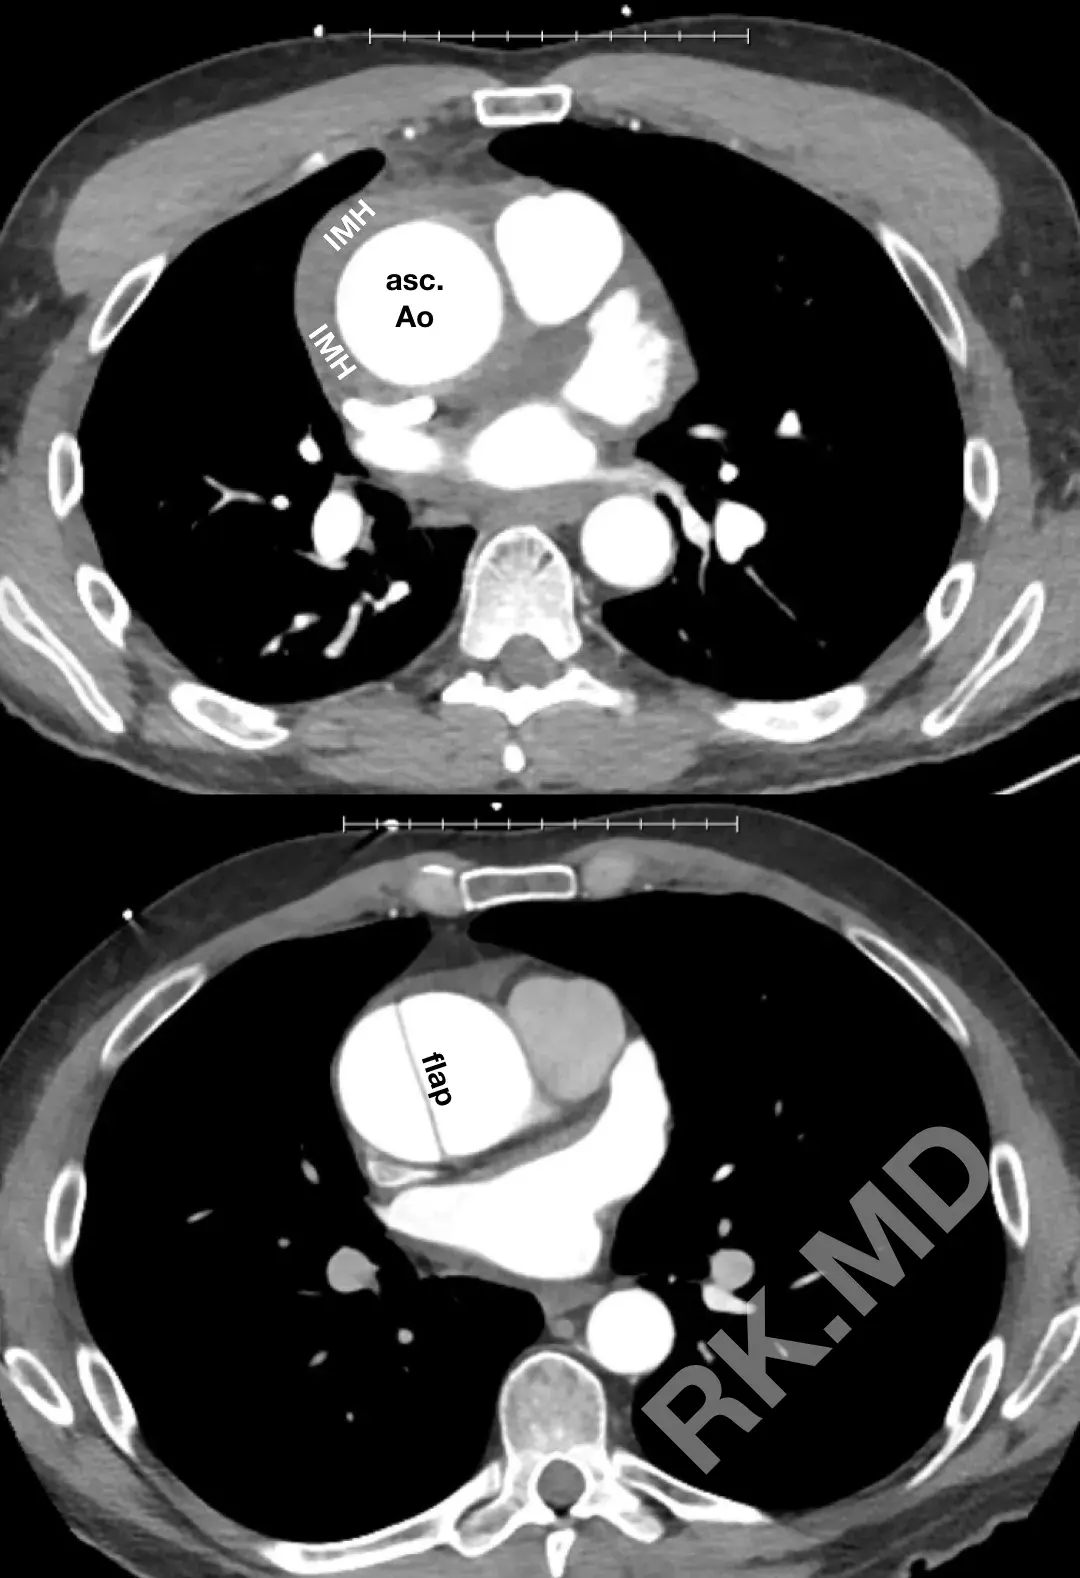

Whereas aortic dissection involves a tear in the intimal (innermost) layer of the aorta, allowing blood to enter the media and creating a false lumen bordered by the intimal flap, IMH is characterized by rupture of the vaso vasorum, leading to hematoma formation in the media layer without a resulting intimal flap. The gold standard for diagnosis (and differentiating the two) is gated CT angiography to evaluate the aortic wall and lumen. Either syndrome can progress to pericardial tamponade, involvement of the aortic valve or coronary arteries, and even aortic rupture.

The management of dissection and IMH is initially centered around achieving impulse control to reduce aortic wall stress; the decision for surgery is dependent on the location of the pathology, evidence of ongoing progression, instability, etc. For example, a type A dissection with evidence of hemodynamic instability and hemopericardium is a surgical emergency whereas a type B IMH can often be medically managed with impulse control and interval imaging.